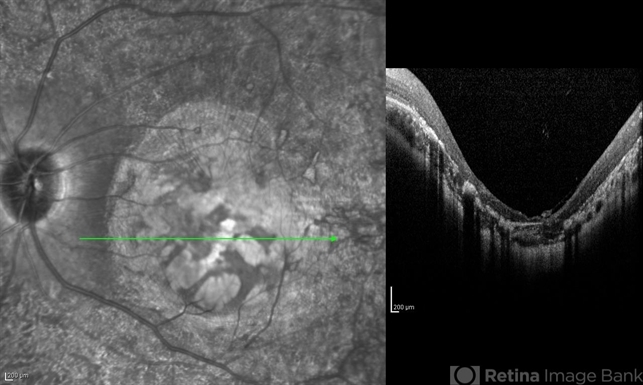

- infrared image, optical coherence tomography (OCT), macular coloboma, bilateral pigmentary retinopathy

- Infrared and OCT images of the left eye of a 25-year-old woman with bilateral macular colobomata and pigmentary retinopathy similar to Leber's congenital amaurosis.